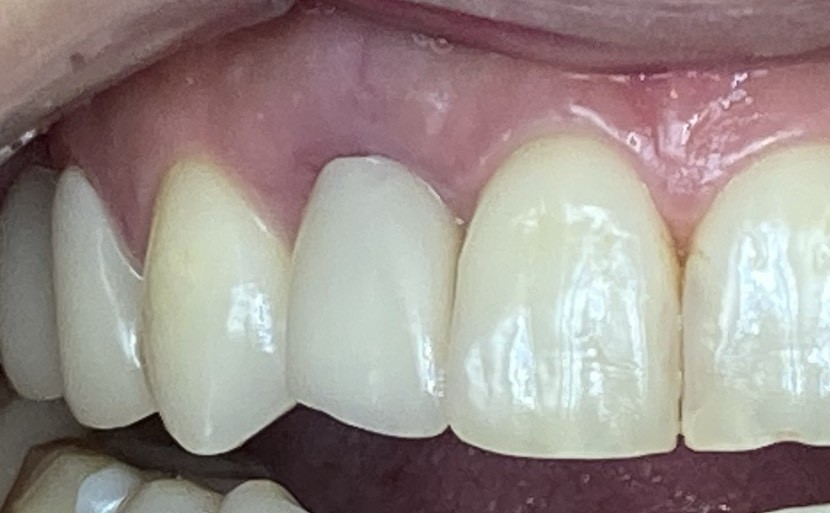

<術前>

割れてしまった右上の前から2番目の歯をインプラントにしていきます。

中で膿んでいるため歯ぐきの色が悪いです。

<処置当日>

割れた歯を抜歯して、インプラントを土台とした仮歯を付けました。